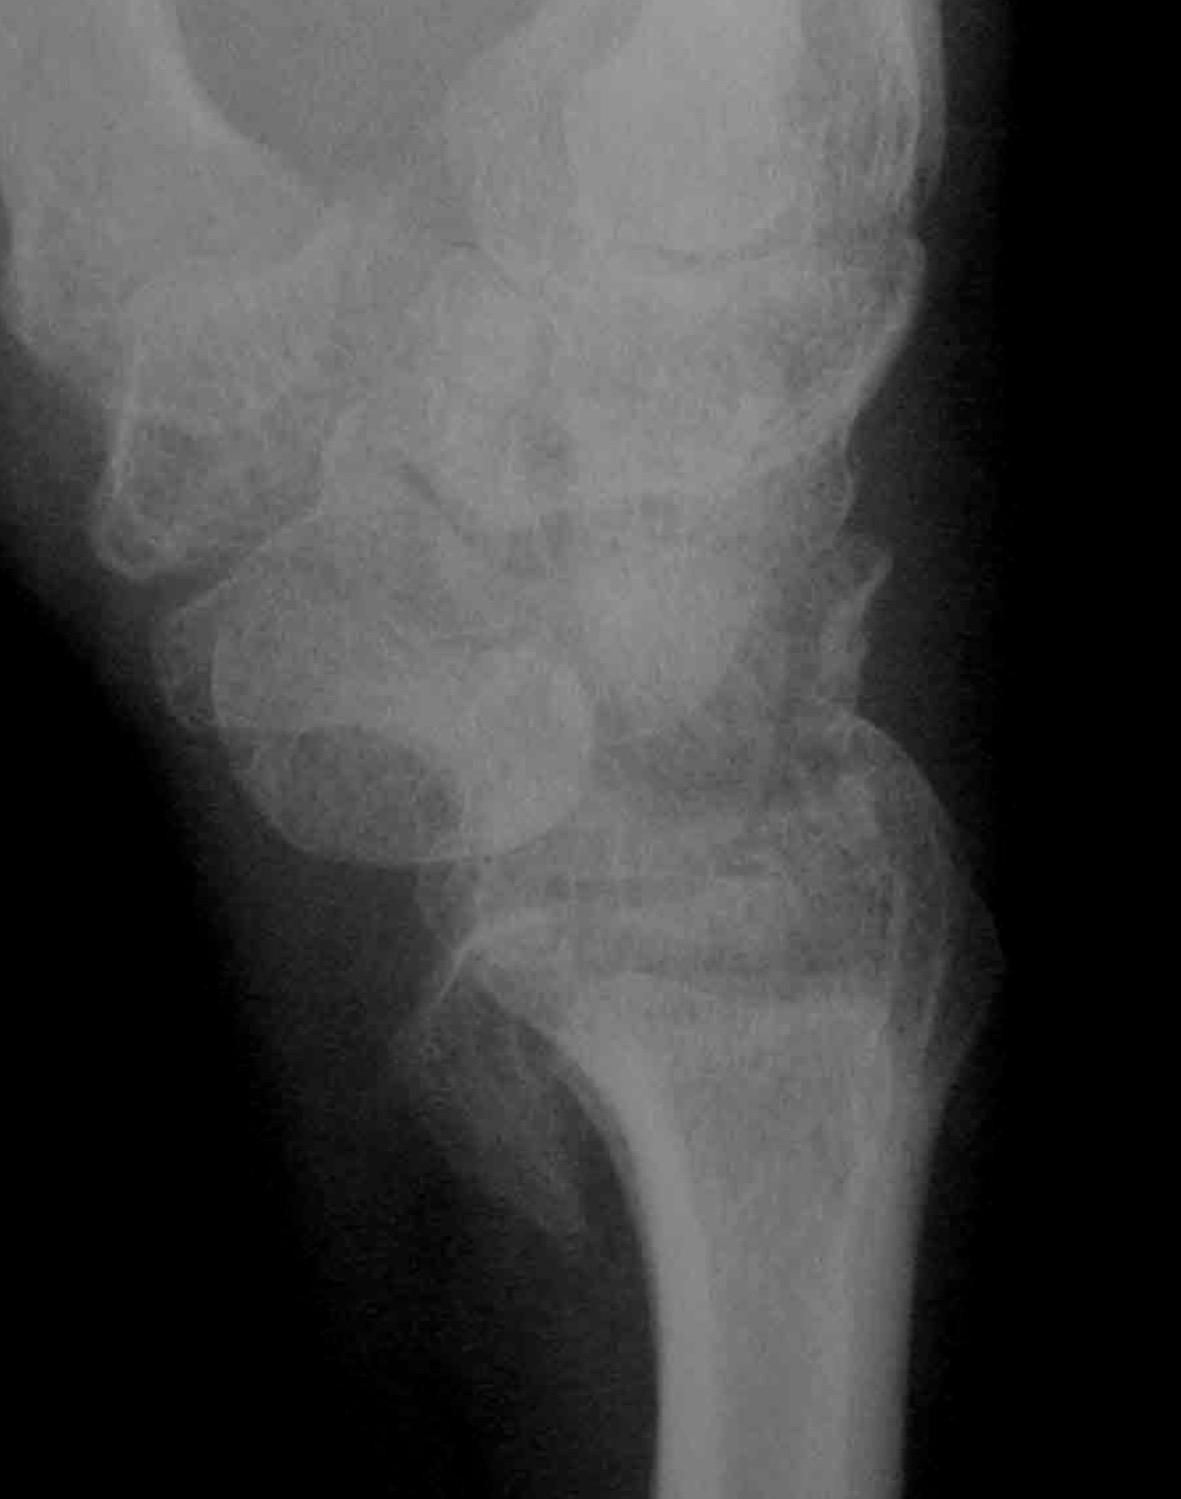

AP X-ray

Disruption of Gilula's 3 smooth carpal arcs / triangular lunate

Normal versus disruputed Gilula's carpal arcs

Piece of pie / triangular appearance of lunate